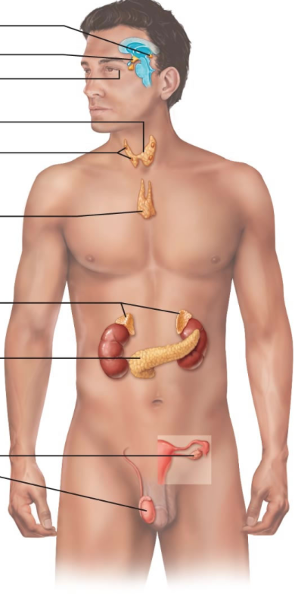

Pituitary Gland

Pineal Gland

Thyroid Gland

Parathyroid Glands-- yellow

Thymus

Adrenal Gland

Pancreas

Gonads